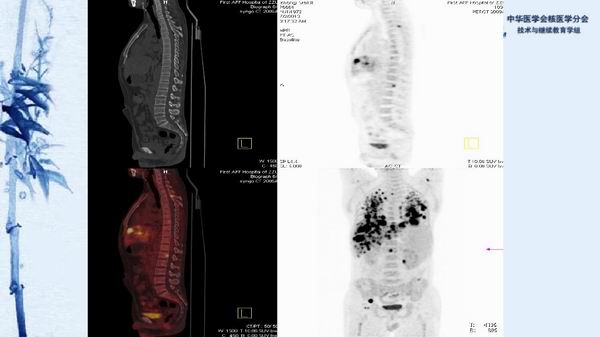

病例49:PET-CT显像诊断淋巴瘤相关噬血细胞综合征一例-【CSNM继教学组】程兵 郑州大学第一附属医院